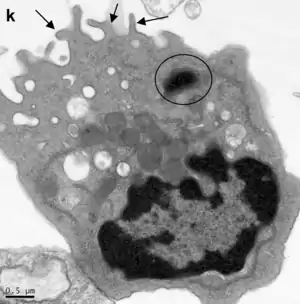

Ultraestructura

Con microscopía electrónica se destaca un extremo apical con microvellosidades cortas y escasas en la luz del bronquiolo.

El retículo endoplasmático es abundante, el aparato de Golgi y los gránulos densos apicales presentan todas las características de una célula de producción y secreción proteica.

El retículo endoplasmático liso genera numerosas vesículas supranucleares. [1]

Las mitocondrias son cortas y numerosas ubicadas en el compartimiento supranuclear.